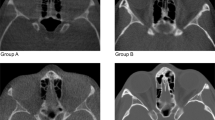

Nowadays, with the increased diffusion of Cone Beam Computerized Tomography (CBCT) scanners in dental and maxillo-facial practice, 3D cephalometric analysis is emerging. Maxillofacial surgeons and dentists make wide use of cephalometric analysis in diagnosis, surgery and treatment planning. Accuracy and repeatability of the manual approach, the most common approach in clinical practice, are limited by intra- and inter-subject variability in landmark identification. So, we propose a computer-aided landmark annotation approach that estimates the three-dimensional (3D) positions of 21 selected landmarks.

The procedure involves an adaptive cluster-based segmentation of bone tissues followed by an intensity-based registration of an annotated reference volume onto a patient Cone Beam CT (CBCT) head volume. The outcomes of the annotation process are presented to the clinician as a 3D surface of the patient skull with the estimate landmark displayed on it. Moreover, each landmark is centered into a spherical confidence region that can help the clinician in a subsequent manual refinement of the annotation. The algorithm was validated onto 18 CBCT images.

Automatic segmentation shows a high accuracy level with no significant difference between automatically and manually determined threshold values. The overall median value of the localization error was equal to 1.99 mm with an interquartile range (IQR) of 1.22–2.89 mm.